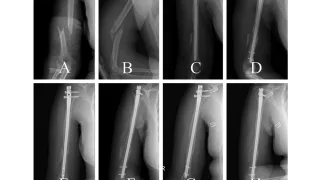

手術日+772日目 2026/4/10(金)(大腿骨転子部逆斜骨折)